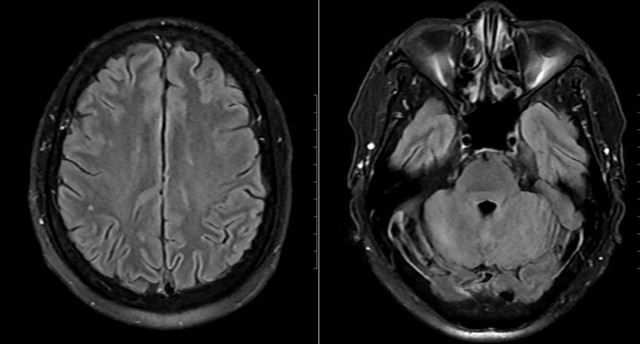

Mặc dù chưa có biểu hiện thần kinh rõ ràng, bệnh nhân vẫn được chọc dò dịch não tủy để loại trừ biến chứng. Kết quả cho thấy dịch não tủy tăng tế bào và protein, phản ứng Pandy dương tính, xác định tình trạng viêm não – màng não. Hình ảnh MRI sọ não còn phát hiện ổ tổn thương nhỏ tại thùy chẩm trái.

Hình ảnh não bệnh nhân có tổn thương.

Sau 24 giờ, bệnh nhân cắt sốt, thể trạng cải thiện rõ. Sau 15 ngày điều trị tích cực, các xét nghiệm và hình ảnh học cho thấy tổn thương hồi phục hoàn toàn, bệnh nhân xuất viện trong tình trạng ổn định, không để lại di chứng thần kinh.